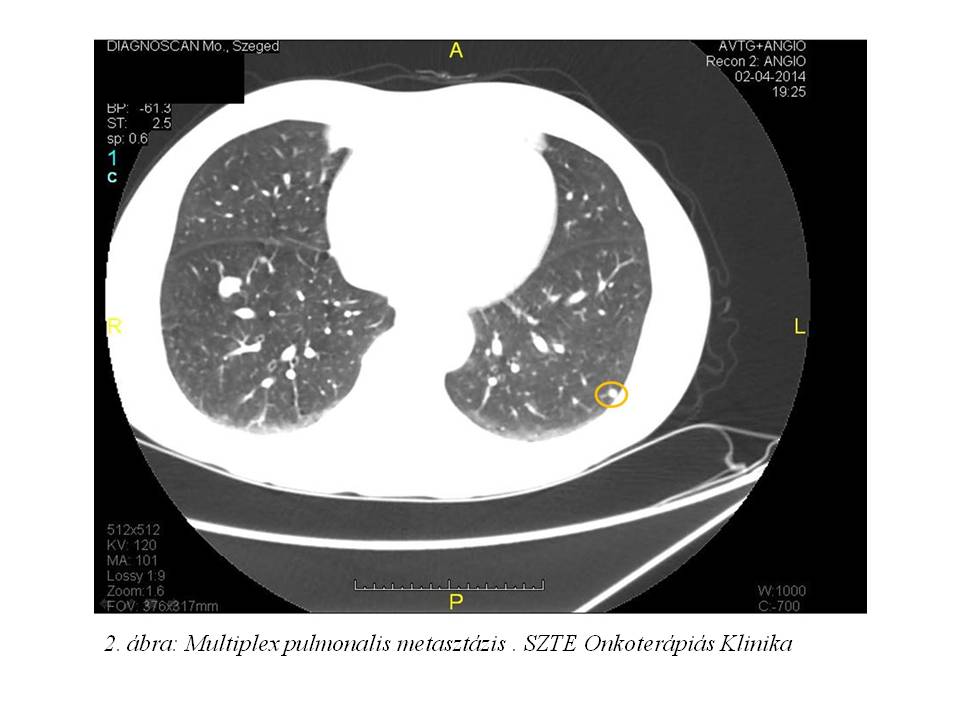

2014.04.02-án készült pelveo-femoralis CT-angiográfián (1. ábra, 2. ábra) a jobb pelvicus régióban nagy kiterjedésű térfoglaló folyamat látszott, mely a csontokat destruálta. Emellett jobb oldali arteria iliaca communis occlusio, multiplex tüdő metastasis is leírásra került. A hasban metastasis nem volt igazolható. 2014.05.06-án a gluteális teriméből biopsia vétel történt, melyből hisztológiai feldolgozás pleimorph liposarcomát véleményezett.